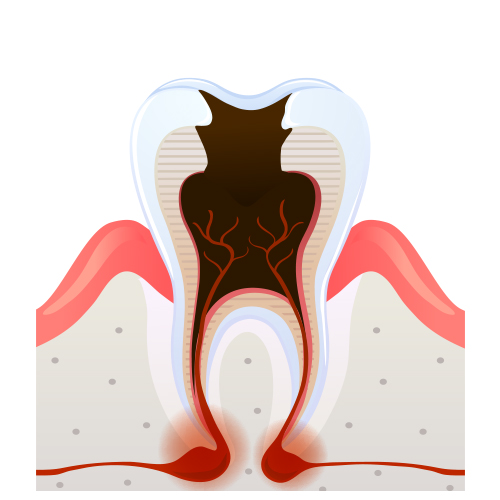

충치의 단계 및 치료법

2단계

상아질까지 진행 시리고 약간의 통증

3단계

신경까지 진행 상당한 통증